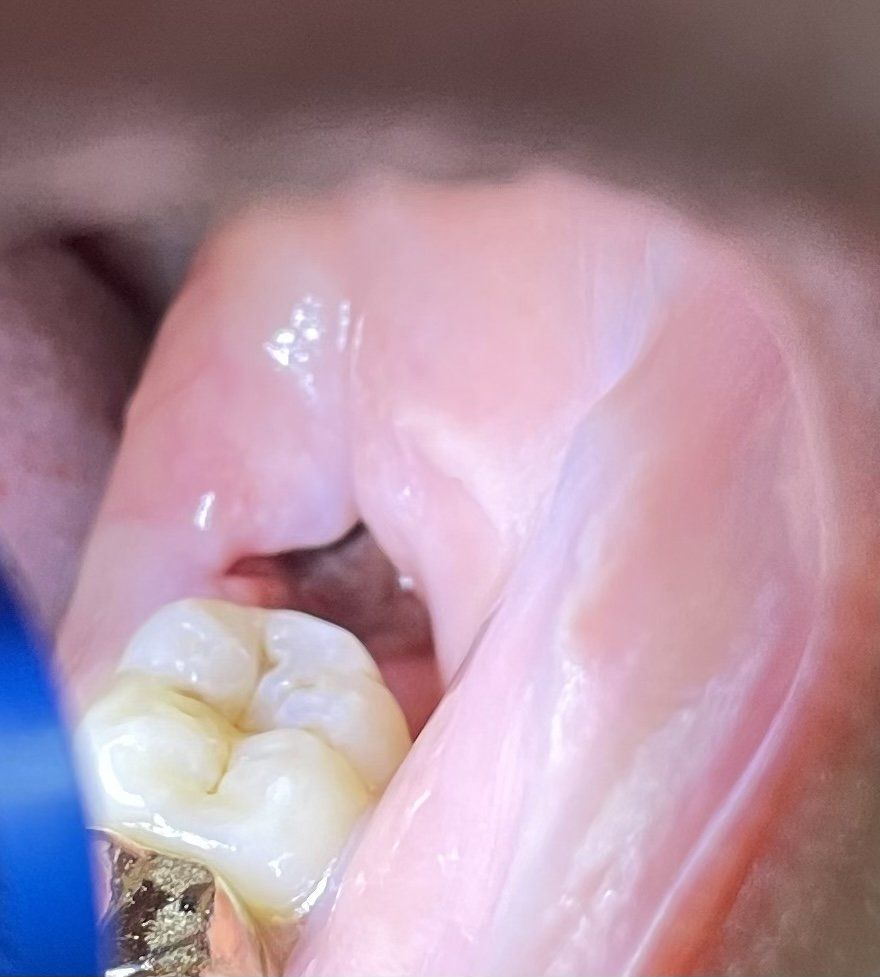

사랑니 발치 육일차 드라이소켓일까요?

누워있는 사랑니 발치 육일차 입니다

사진이 잘 찍히지는 않으나 불투명한 하얀색 막으로 쌓여있는 것 같은데 드라이 소켓 증상음 아닌가요?

윗 부분에 막히지 않은 깊은 틈도 있습니다

사진상 발치부위의 혈병이 초기에 제거되어 잇몸이 덜 아문것 같아 보이기는 하지만 드라이 소켓으로 보이지는 않습니다.

드라이 소켓은 구강내에 치조골이 노출되어 감염이 되는것으로 사진에 보이는 하얀막은 치조골로 보이지 않아요.

정상적인 치료 과정으로 보여집니다. 혈병이 사라지고 섬유화되는 과정에서 나타나는 현상입니다. 드라이소켓은 발치 이후 2~3일 시점에서 갑자기 급격한 통증을 동반하면서 혈병이 떨어지는 것을 말하며 7일 이후에 나타난 것을 드라이소켓이라고 하지 않습니다. 또한 사진으로 보아 매우 잘 회복되고 있는 것으로 보여집니다.

사랑니 발치후 발치공간이 아직 치유가 다 되지 않아서 저렇게 보이는겁니다. 드라이소켓은 염증의 일종으로 극심한 통증과 냄새가 나게 됩니다. 크게 걱정하실껀 아니고, 식사하시고 음식물이 남지 않게 물로 오물오물해서 잘 헹궈주세요.

사진으로 봤을때 드라이소켓으로 보이진 않고, 정상적인 치유과정으로 보입니다.

하얀막은 잇몸이 치유되는 조직으로 보입니다.